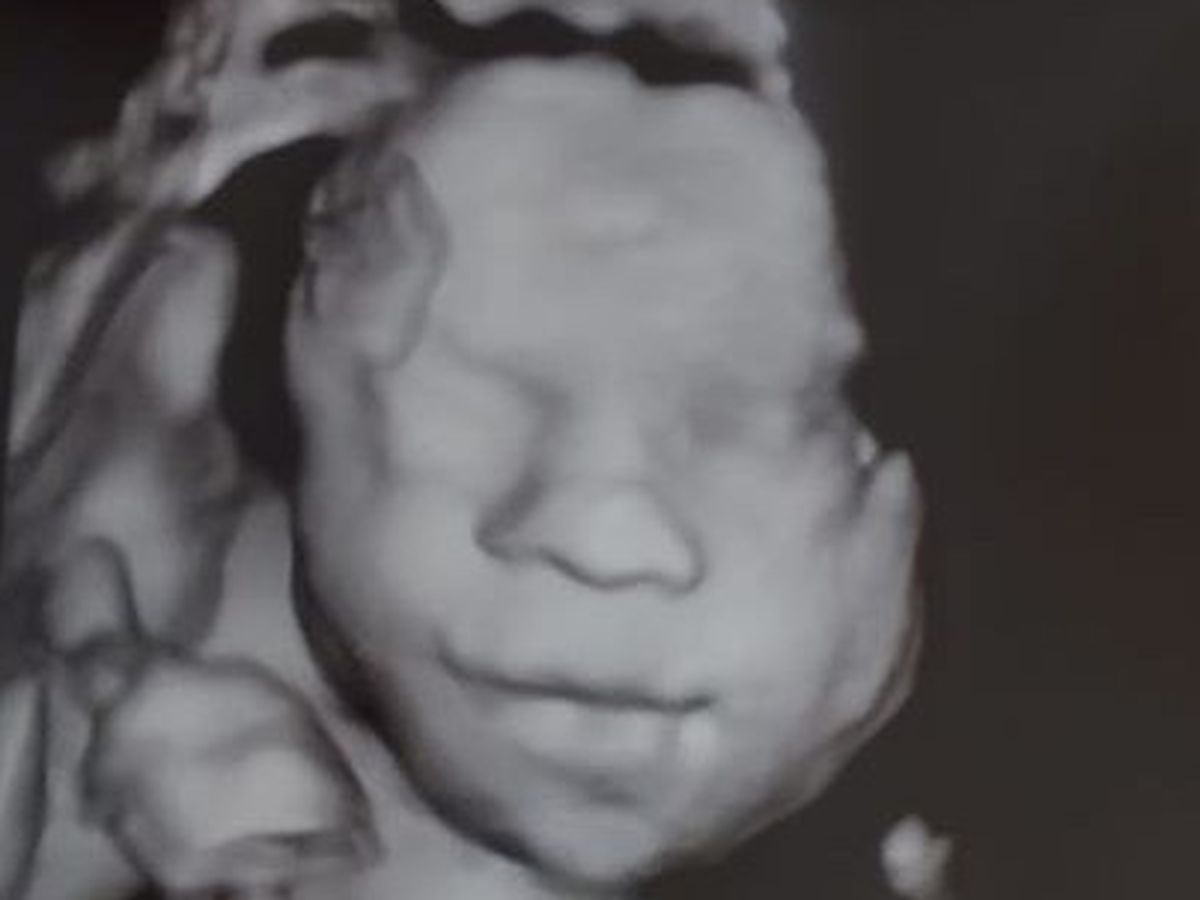

Heather and Chris's baby Waylon has congenital diaphragmatic hernia (CDH). He will be born at John Hopkins ALL Children's Hospital in St. Petersburg FL on October 5th unless there is a reason for him to come earlier than that . You can go to his Blog if you would like to read more. https://www.facebook.com/Warrior-Waylon-114254700330583/

Heather and Chris are from Allegan Michigan and have 3 other children. The baby will be born at John Hopkins ALL Children's Hospital in St. Petersburg, Florida and they will be there for months (the length of time is undetermined). There will be medical bills, travel expenses, food expenses, Right now the Ronald McDonalds house is closed due to Covid so we are still working those details out, because Heather has to be near the hospital after she is 36 weeks pregnant. I am sure you can see there will be expenses beyond the normal expenses of bringing a healthy baby into the world. . Heather just had her first two appointments at John Hopkins children's hospital and they are giving Waylon a 95% survival rate but at other Children's hospitals he was only given 30%. He will have one surgery right after birth to fix the CDH and then another surgery after that for acid reflux. There are other procedures that may be necessary depending on his lung function. There will be appointments at John Hopkins all childrens hospital once the baby is released. It is absolutely necessary for Waylon to be born at John Hopkins All Children's hospital.